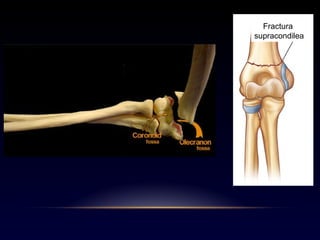

Fractura

supracondilea

Clínicamente hay edema y deformidad

Es importante descartar lesiones

del nervio interóseo anterior,

con la flexión de la interfalángica

distal de índice y pulgar,

y descartar lesiones del nervio radial

Fractura supracondilea

de húmero

La inmovilización

se hace en la posición

en la que llega el paciente,

extensión completa o semiflexión,

y así no aumentar la compresión neurovascular